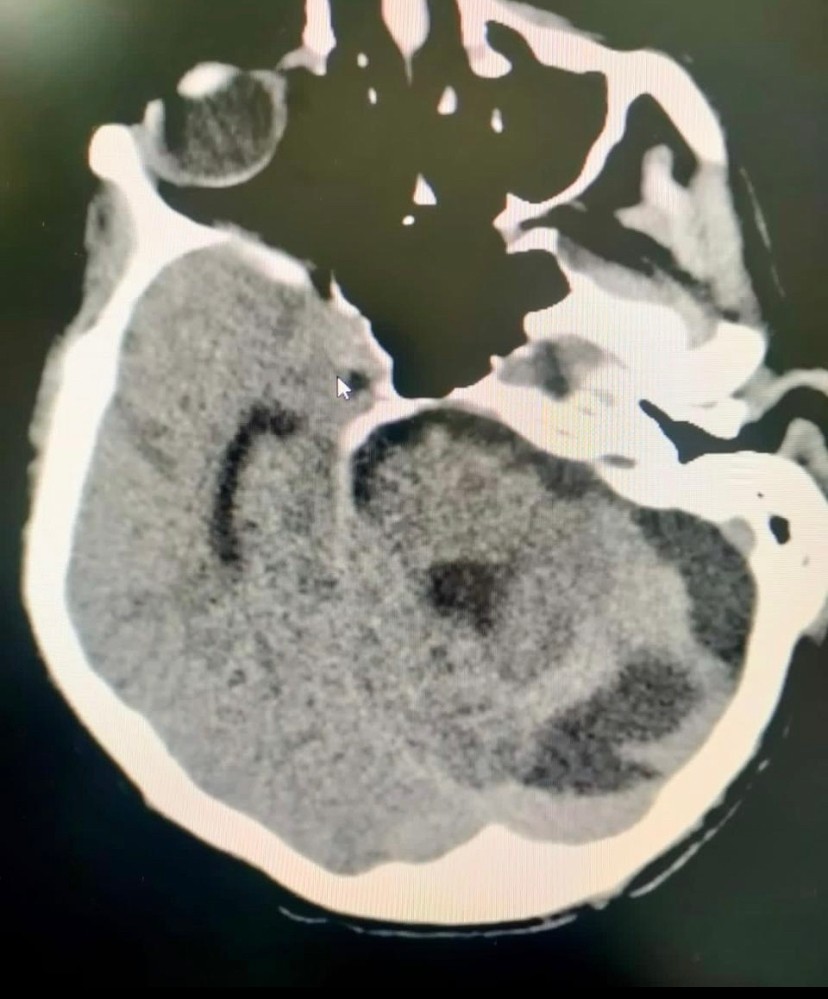

نجح فريق طبي بمستشفى الملك عبدالله ببيشة في انقاذ مواطن في العقد الخامس من العمر كان يعاني من نزيف حاد في الدماغ.

قالت صحة بيشة ، أنه تم استقبال المريض بقسم الطوارئ وهو فاقد للوعي وتم عمل الفحوصات اللازمة واتضح وجود نزيف حاد بالدماغ ، قرر الفريق الطبي إجراء العملية على وجه السرعة إذ تم تحويله إلى غرفة العمليات.

واضافت صحة بيشة ، تكللت العملية بالنجاح - ولله الحمد - وتم نقل المريض إلى العناية الفائقة لمتابعة الحالة ، تحسنت حالة المريض وتم خروجه من المستشفى.